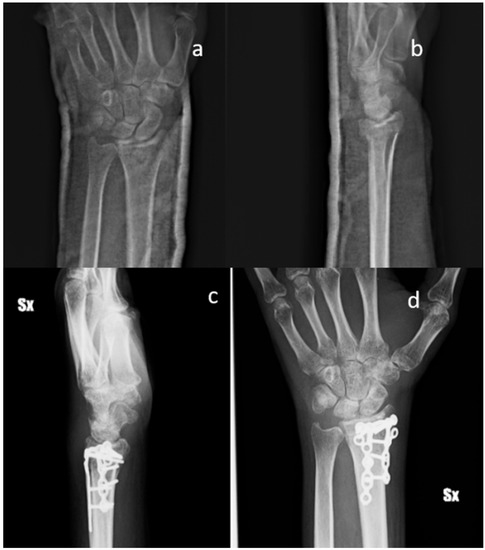

Figure 2.

Standard X-ray of a displaced articular fracture of the distal radius associated with styloid ulna fracture. Preoperative images in AP (a) and Lateral (b) view are compared to post-operative X Ray at 2 months (c,d). The exuberant callus formation can be visualized (Male, 55 yy).